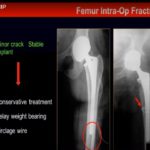

Nailing Vs Plating for Distal Femoral Periprosthetic fractures

Courtesy: Cory Collinge, MD, Professor of Orthopaedic Surgery, Orthopaedic Trauma Service, Vanderbilt University, Nashville, TN Saqib Rehman MD, Associate Professor, Director of Orthopaedic Trauma, Temple University, Philadelphia, Pennsylvania, USA www.orthoclips.com From the 8th Annual Philadelphia Orthopaedic Trauma Symposium, June 10, 2016 at Lewis Katz School of Medicine at Temple University

Peri prosthetic Fractures: Advances in Management

COurtesy: Dr DD Tanna, Ashok Shyam, IORG, OrthoTV